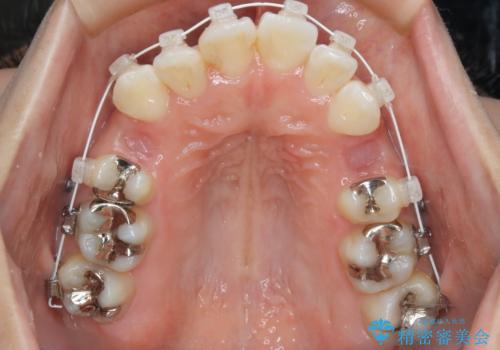

- 歯のガタつきと出っ歯が気になるので矯正治療を希望し来院された患者様です。

上下顎とも歯を並べられるスペースが無く、口元を下げたいというご希望だったので、抜歯とワイヤー矯正を併用した治療を計画しました。

抜歯スペースを利用し口元を大きく下げることが出来ました。